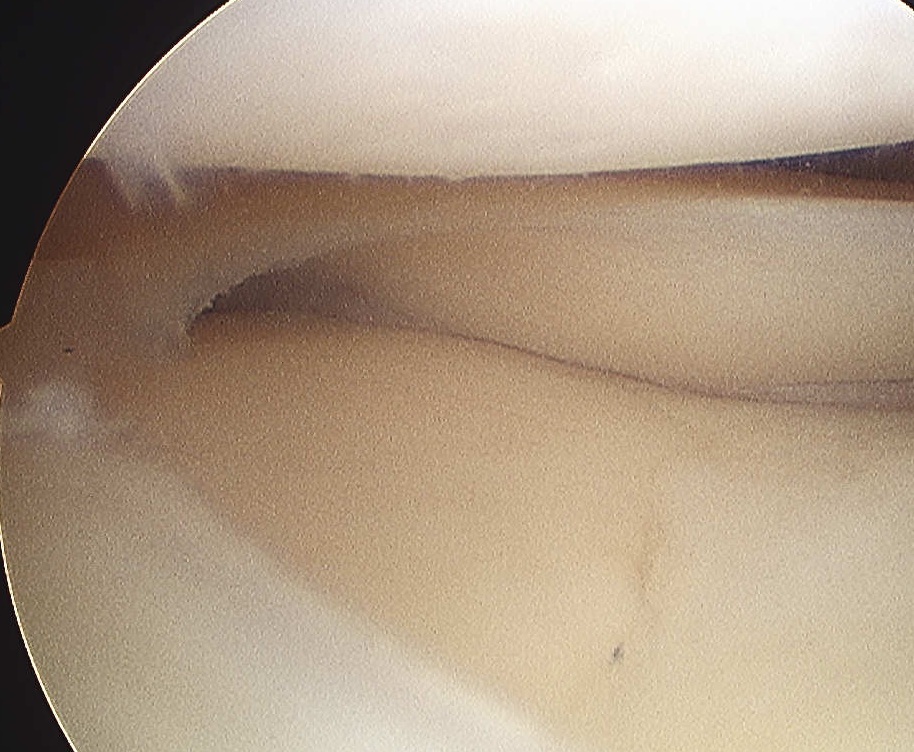

1. Arthroscopic resection of tear

Tear may be difficult to identify

- careful inspection & probing

- often on undersurface of meniscus

- probe passed through tear into cyst

- usually results in decompression of cyst

- defunction flap valve with meniscectomy